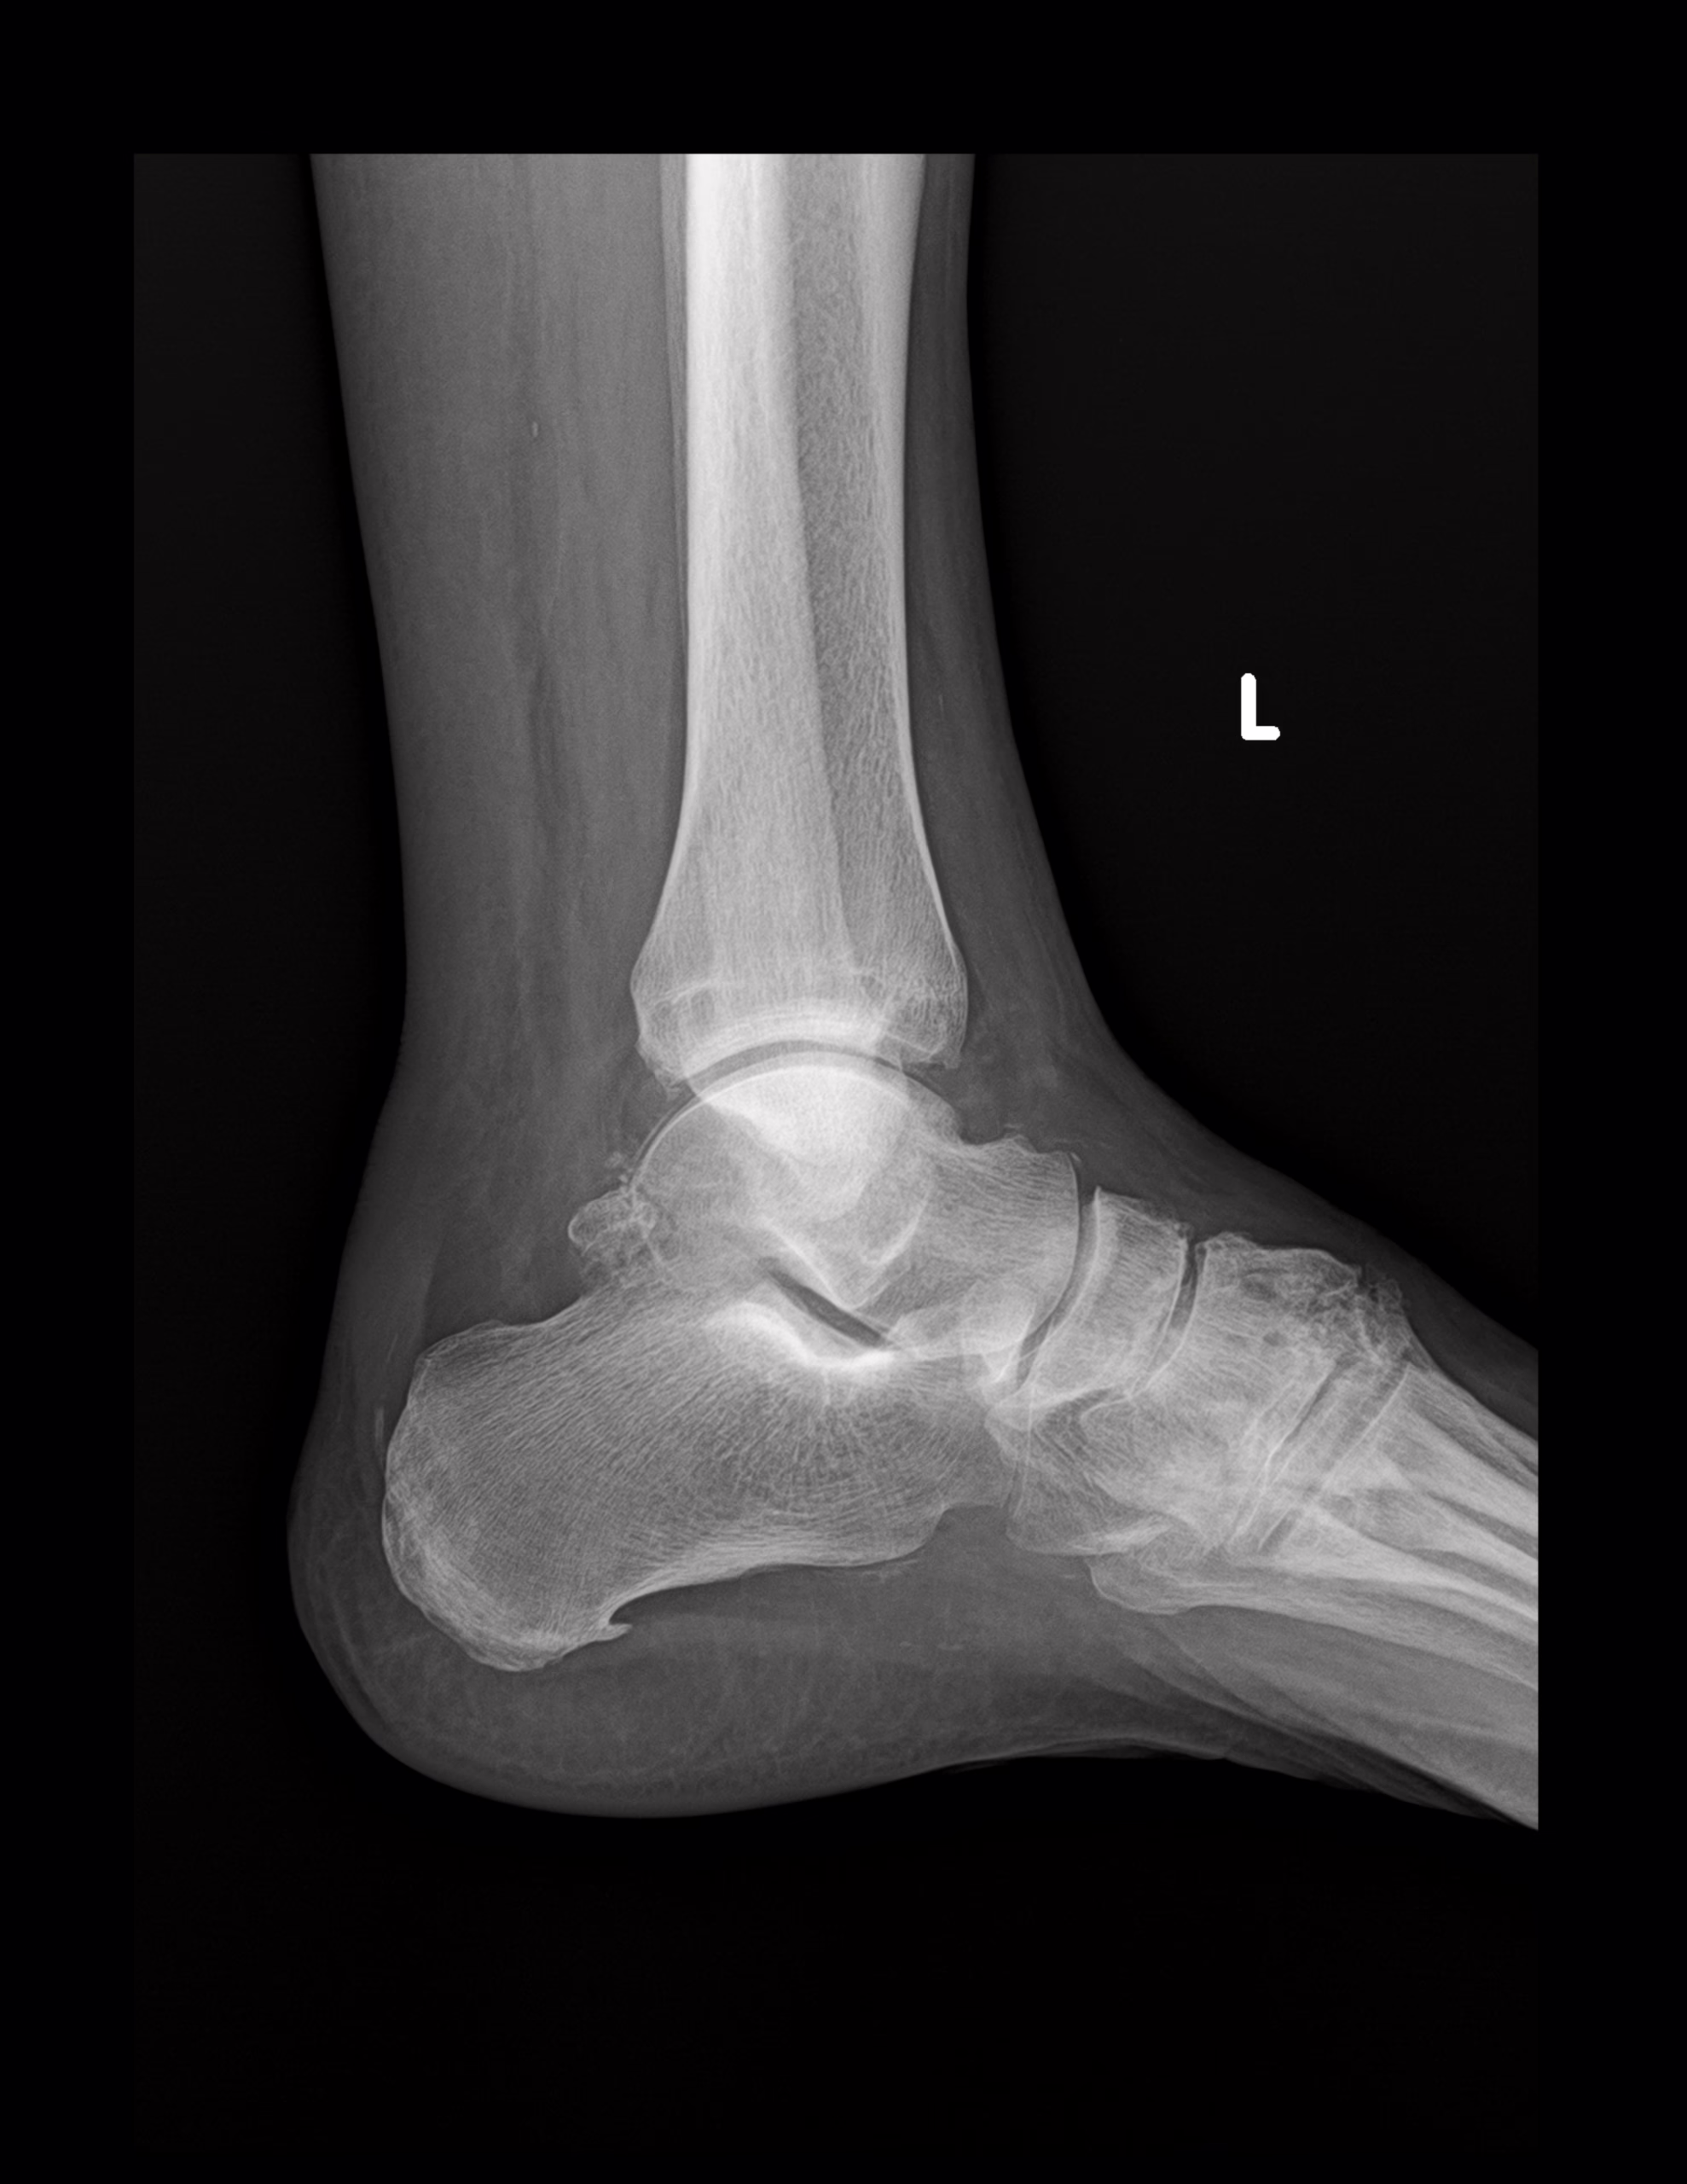

RADIOGRAFIA AP Y LATERAL DE TOBILLO

LAS PROYECCION RADIOLOGICA OBTENIDA NOS MUESTRA LOS SIGUIENTES HALLAZGOS

-Tejidos blandos, con aumento de la densidad y grosor a nivel posterior.

-De lo observado de tibia y peroné, sin evidencia de lesiones líticas, blásticas o perdida de la contigüidad.

-Existe fractura a nivel de proceso posterior de astrágalo con involucro de porción superior del calcáneo. Existe espícula osteofítica en porción inferior de tuberosidad del calcáneo. Resto de huesos del tarso y metatarsos, sin evidencia de lesiones líticas, blásticas o perdida de la contigüidad.

-Angulo de Bohler de 53.1 °

-De lo observado de espacios articulares, sin evidencia de alteraciones.

OPINIÓN RADIOLÓGICA:

EN EL PRESENTE ESTUDIO RADIOGRÁFICO, EXISTE FRACTURA DEL PROCESO POSTERIOR DEL ASTRÁGALO E INVOLUCRO SUPERIOR DEL CALCÁNEO, CON EDEMA ASOCIADO.